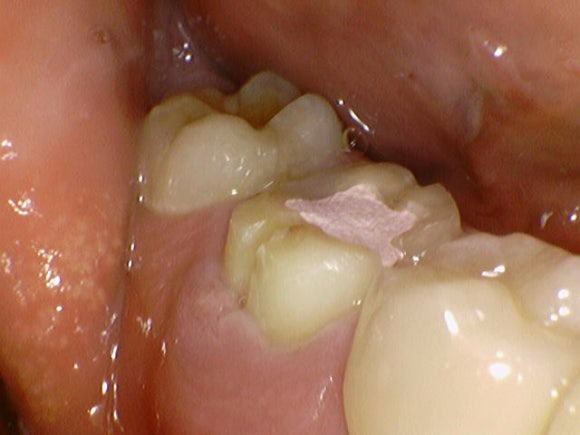

20250201

재신경치료를 시작했습니다.

치아 내부를 깨끗이 청소하여

염증의 원인을 제거합니다.

잇몸의 붓기는 금새 좋아집니다.